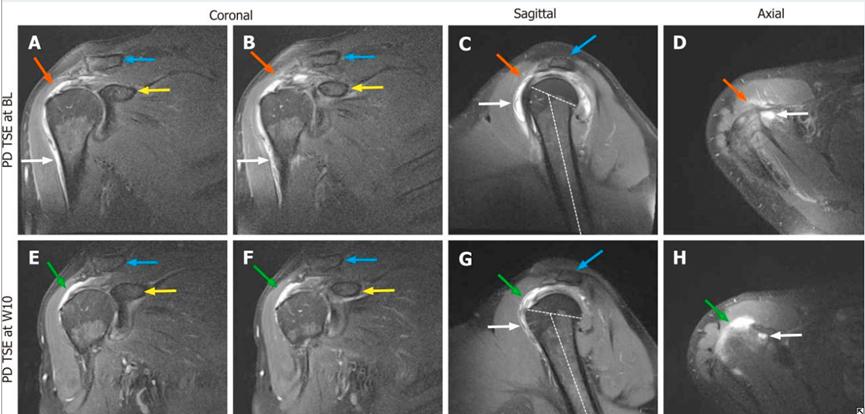

图1:外伤后18天右肩MRI(A-D);自体脂肪干细胞治疗后10周(E-H) 图片来源:文献[1]

治疗结果:自体脂肪干细胞治疗后10周后复查对照右肩(冈上肌)MRI可见:创伤相关的淤血明显减少,冈上肌注射部位可见MRI高信号结果形成,ASES评分增加至79分。未经干细胞治疗部位(冈下肌)MRI可见:肌腱撕裂加重,需要手术修复。